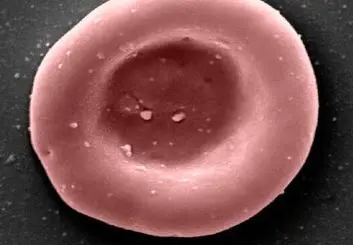

• نخستین انتقال خون با سلول‌های پرورش‌یافته در آزمایشگاه انجام شد

نخستین انتقال خون با سلول‌های پرورش‌یافته در آزمایشگاه انجام شد